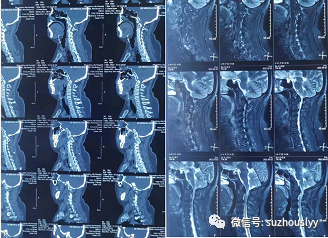

患者,男,47岁,因颈背部疼痛伴双上肢麻木、下肢无力、跛行入院。就诊当地医院行辅助检查可见MR见颈2/3、3/4椎间盘层面椎管狭窄,延髓内脊髓变性。颈椎CT见寰椎与枕骨局部融合,寰椎后弓未融合,颈2及颈3椎体、椎板及棘突融合。当地医院建议手术治疗,因该手术难度及风险极大,建议外院治疗。患者辗转数家医院后,就诊我院脊柱外科,经专家诊断为:颅底陷凹症、寰椎后弓二分裂、先天性颈3、4融椎并发育性寰椎管狭窄症。枕骨大孔狭窄及发育性寰椎管狭窄压迫到延髓可以有呼吸窘迫等严重症状,并可出现类似于下颈椎的脊髓病变:感觉和运动功能障碍,行走障碍,括约肌功能障碍和共济失调等。一旦出现脊髓神经受压症状,应考虑手术治疗。脊髓减压可以根据受压部位选择前路或后路手术,固定多考虑采用寰枕融合术或椎弓根钉固定并融合。通过C0-C5椎管减压解除压迫、避免进一步脊髓损伤,进行后路脊柱固定和融合保持脊柱稳定性。